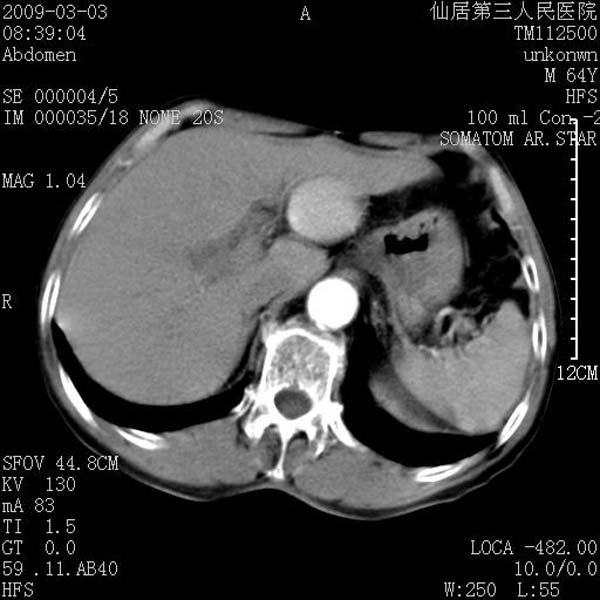

标题: CT18469:男性,64y,体检B超示肝脏低回声肿块,有胃溃疡手术 [打印本页]

患者,男性,64y,体检b超示肝脏低回声肿块,有胃溃疡手术史。

考虑----胃肠道间质瘤可能性大

从平扫及增强的特点来看,支持肝脏腺瘤并出血。

考虑胃间质瘤可能性大。

胃肠道间质瘤!

ct值呢?感觉没强化,象囊性。

考虑肝静脉韧带裂区良性占位性病变(囊肿?)。

考虑肝囊肿并出血可能性大.

考虑高密度囊肿可能性大